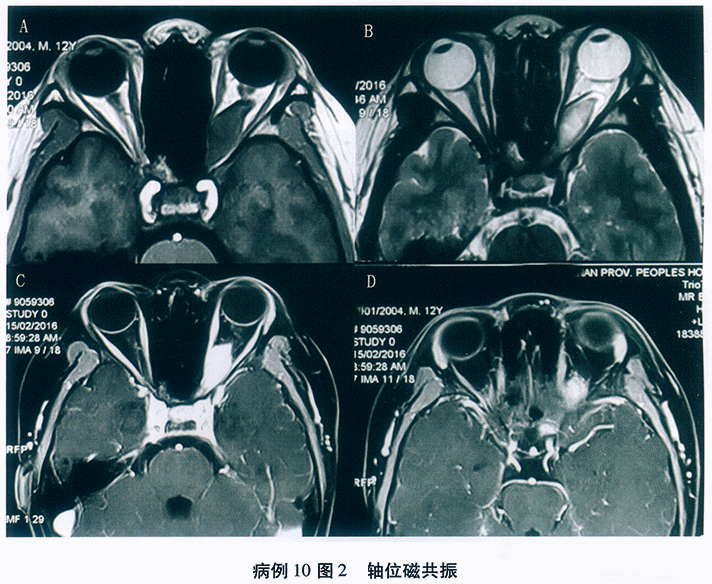

问题 1176

患者,男性, 28岁,主诉“双眼先后眼红、畏光、流泪、异物感9天, 左眼视力下降2天”。患者半月前曾至公共浴室洗浴,其后出现左眼红, 流泪,异物感等症状, 无明显分泌物,2天后右眼亦出现同样症状, 去医院就诊为“急性结膜炎”,予以局部抗病毒、抗生素滴眼液治疗, 但病情进一步发展,而且左眼出现视力下降, 遂至我院就诊。